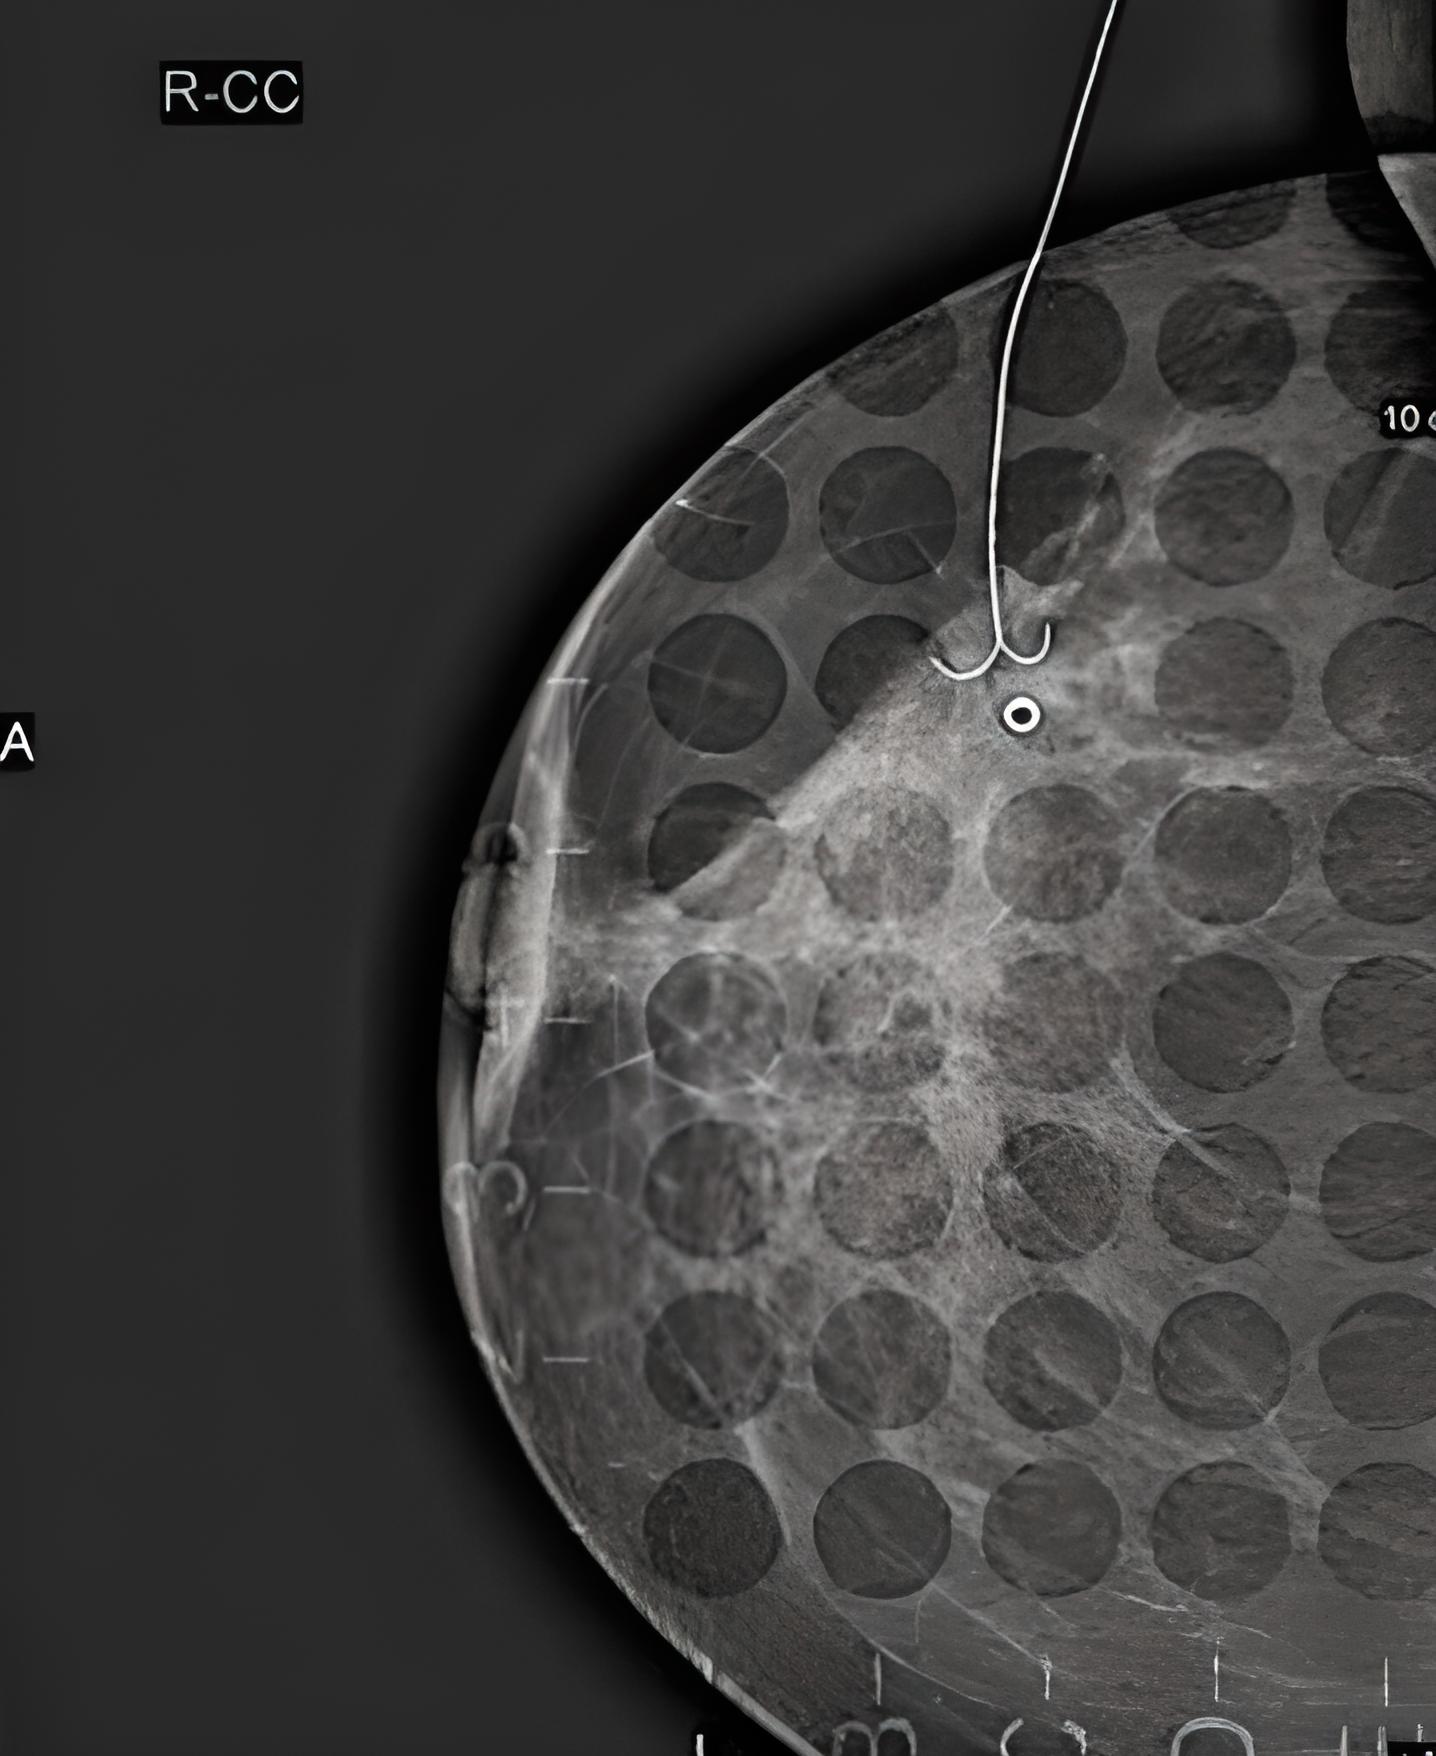

Mammographie Tut Das Weh. Digital mammography at the Radiologie München Dieses Zusammendrücken kann unangenehm, manchmal auch schmerzhaft sein Warum tut Mammographie weh? Um das Brustgewebe gut darstellen zu können, wird die Brust kurz zusammengedrückt

Einige Experten sind der Ansicht, dass das Mammographie-Screening mehr schadet als nützt Tut die Mammographie weh? Manchmal kann das Zusammendrücken der Brüste zwischen den beiden Plexiglas-Scheiben etwas unangenehm oder sogar leicht schmerzhaft sein

Dieses Zusammendrücken kann unangenehm, manchmal auch schmerzhaft sein Tut die Mammographie weh? Bei der Mammographie macht die Röntgenassistentin von jeder Brust zwei Mammographie-Bilder Geburtstag erhält jede Frau eine Einladung zum Mammographie-Screening

Mammographie Was ist das? Mammographie Screening Bonn RheinSieg Euskirchen. Habe vor Kurzem einen Überweisungsschein zur Mammographie von meiner Frauenärztin bekommen, aufgrund eines kleinen Knoten in der Brust, welchen sie entdeckt hat Die Mammographie spielt jedoch eine zentrale Rolle in der Früherkennung von Brustkrebs und ist ein wichtiger Schritt zur Vorsorge.

Gesundheitslexikon Mammographie. Deine Brust wird dabei ein bisschen zusammengedrückt und zwischen 2 Platten geschoben. Doch die Aufklärung über das Mammographie-Screening ist lückenhaft